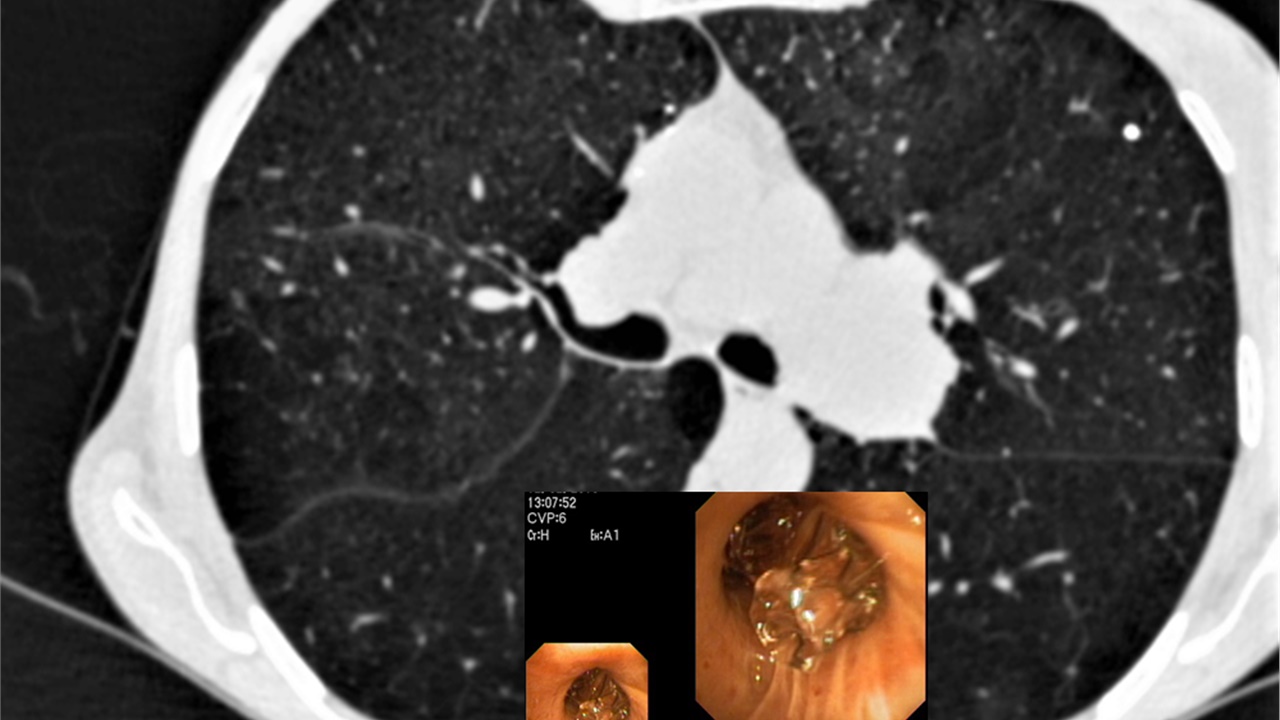

Bronchoscopy On Air #1: Peripheral Pulmonary Lesion / Rebiopsy

Whatch Live on 24 April 2021, 10:00 CEST. A video presentation of a case with peripheral pulmonary lesion approach for lung Ca. Followed by Live discussion by a group of experts....